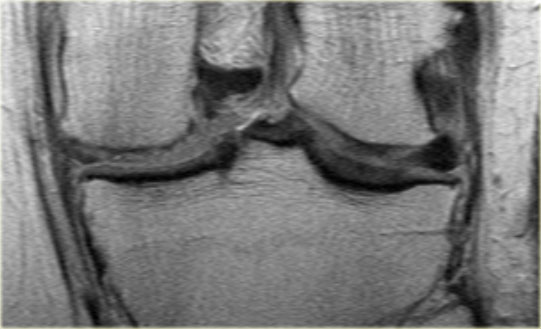

Đây là một trường hợp điển hình khác của rách chân sụn chêm trong.

Lưu ý rằng trường hợp này còn kèm theo hình ảnh sụn chêm ngoài dạng đĩa.

Đây là một trường hợp rách chân sụn chêm trong khác.

Lưu ý rằng sừng sau không còn bám vào xương chày.

Thay vào đó, có thể thấy một khoảng hở (mũi tên cong).

Những tổn thương rách này rất dễ bị bỏ sót khi người đọc nhầm tưởng sừng sau vẫn bình thường.